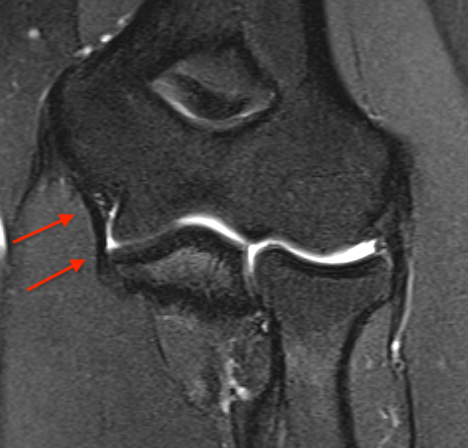

MRI

Bony avulsion UCL complex medial epicondyle

PRLIPLRI

Bony avulsion UCL sublime tubercle